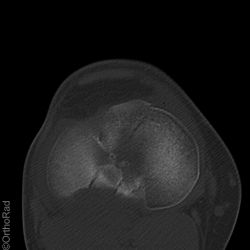

Tibiakopffraktur (nicht disloziert)